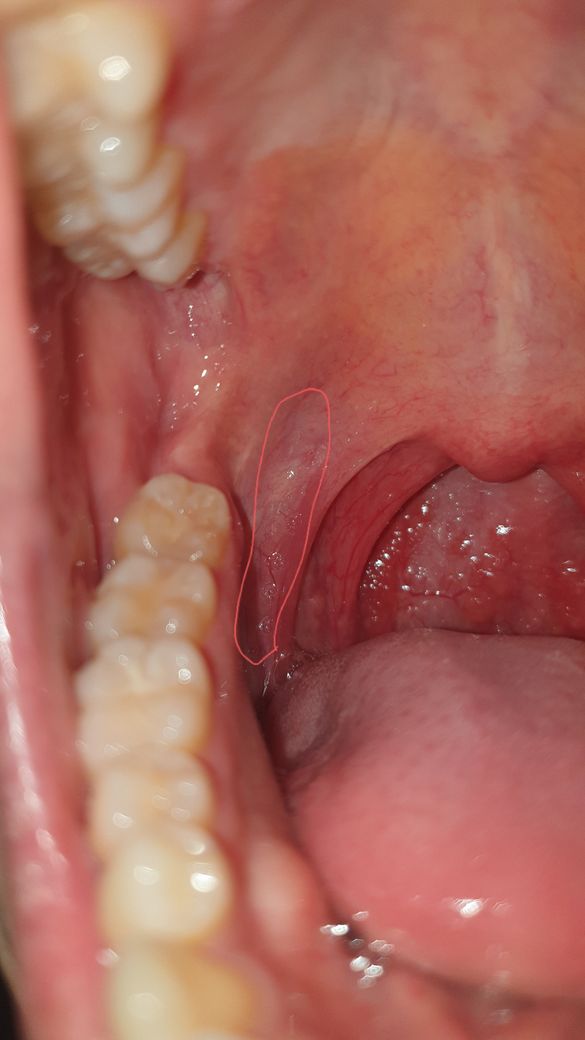

1 2 사진에서처럼 양쪽 막 근처에 살짝 하얗게 되어있고 안쪽으로는 충혈된 것처럼 빨간 느낌입니다

인후부를 사진으로 보았을 때 인후 발적과 함께 왼쪽 편도가 조금 부어 있지만

편도 농양으로 보이지는 않으며 인후통을 동반한 일반적인 감기 증상과 같은 것으로 보입니다.

사진을통하여봤을때는 발적을 동반한 염증이 있어서 목넘김이 힘들고 불편한것으로 생각이됩니다.